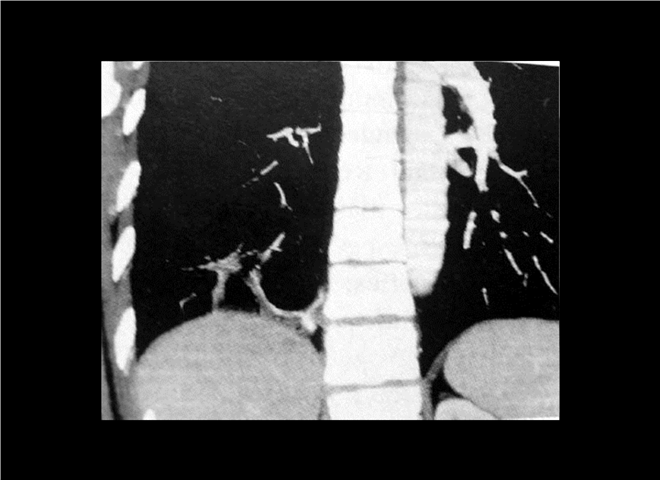

13_CT增强扫描